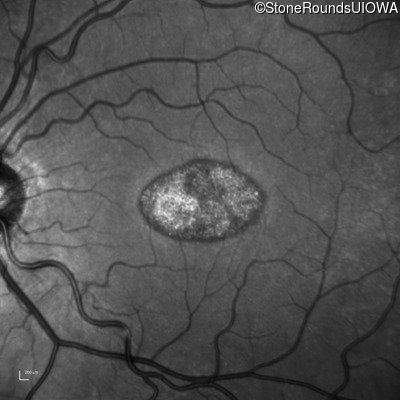

This 22 year old man had macular abnormalities noted incidentally at a routine eye exam at age 19. Since then, he has experienced a gradual loss of acuity particularly in the left eye.

| AR Stargardt Disease | ABCA4 | Tyr245Stop TAT>TAG | Unknown | AR |